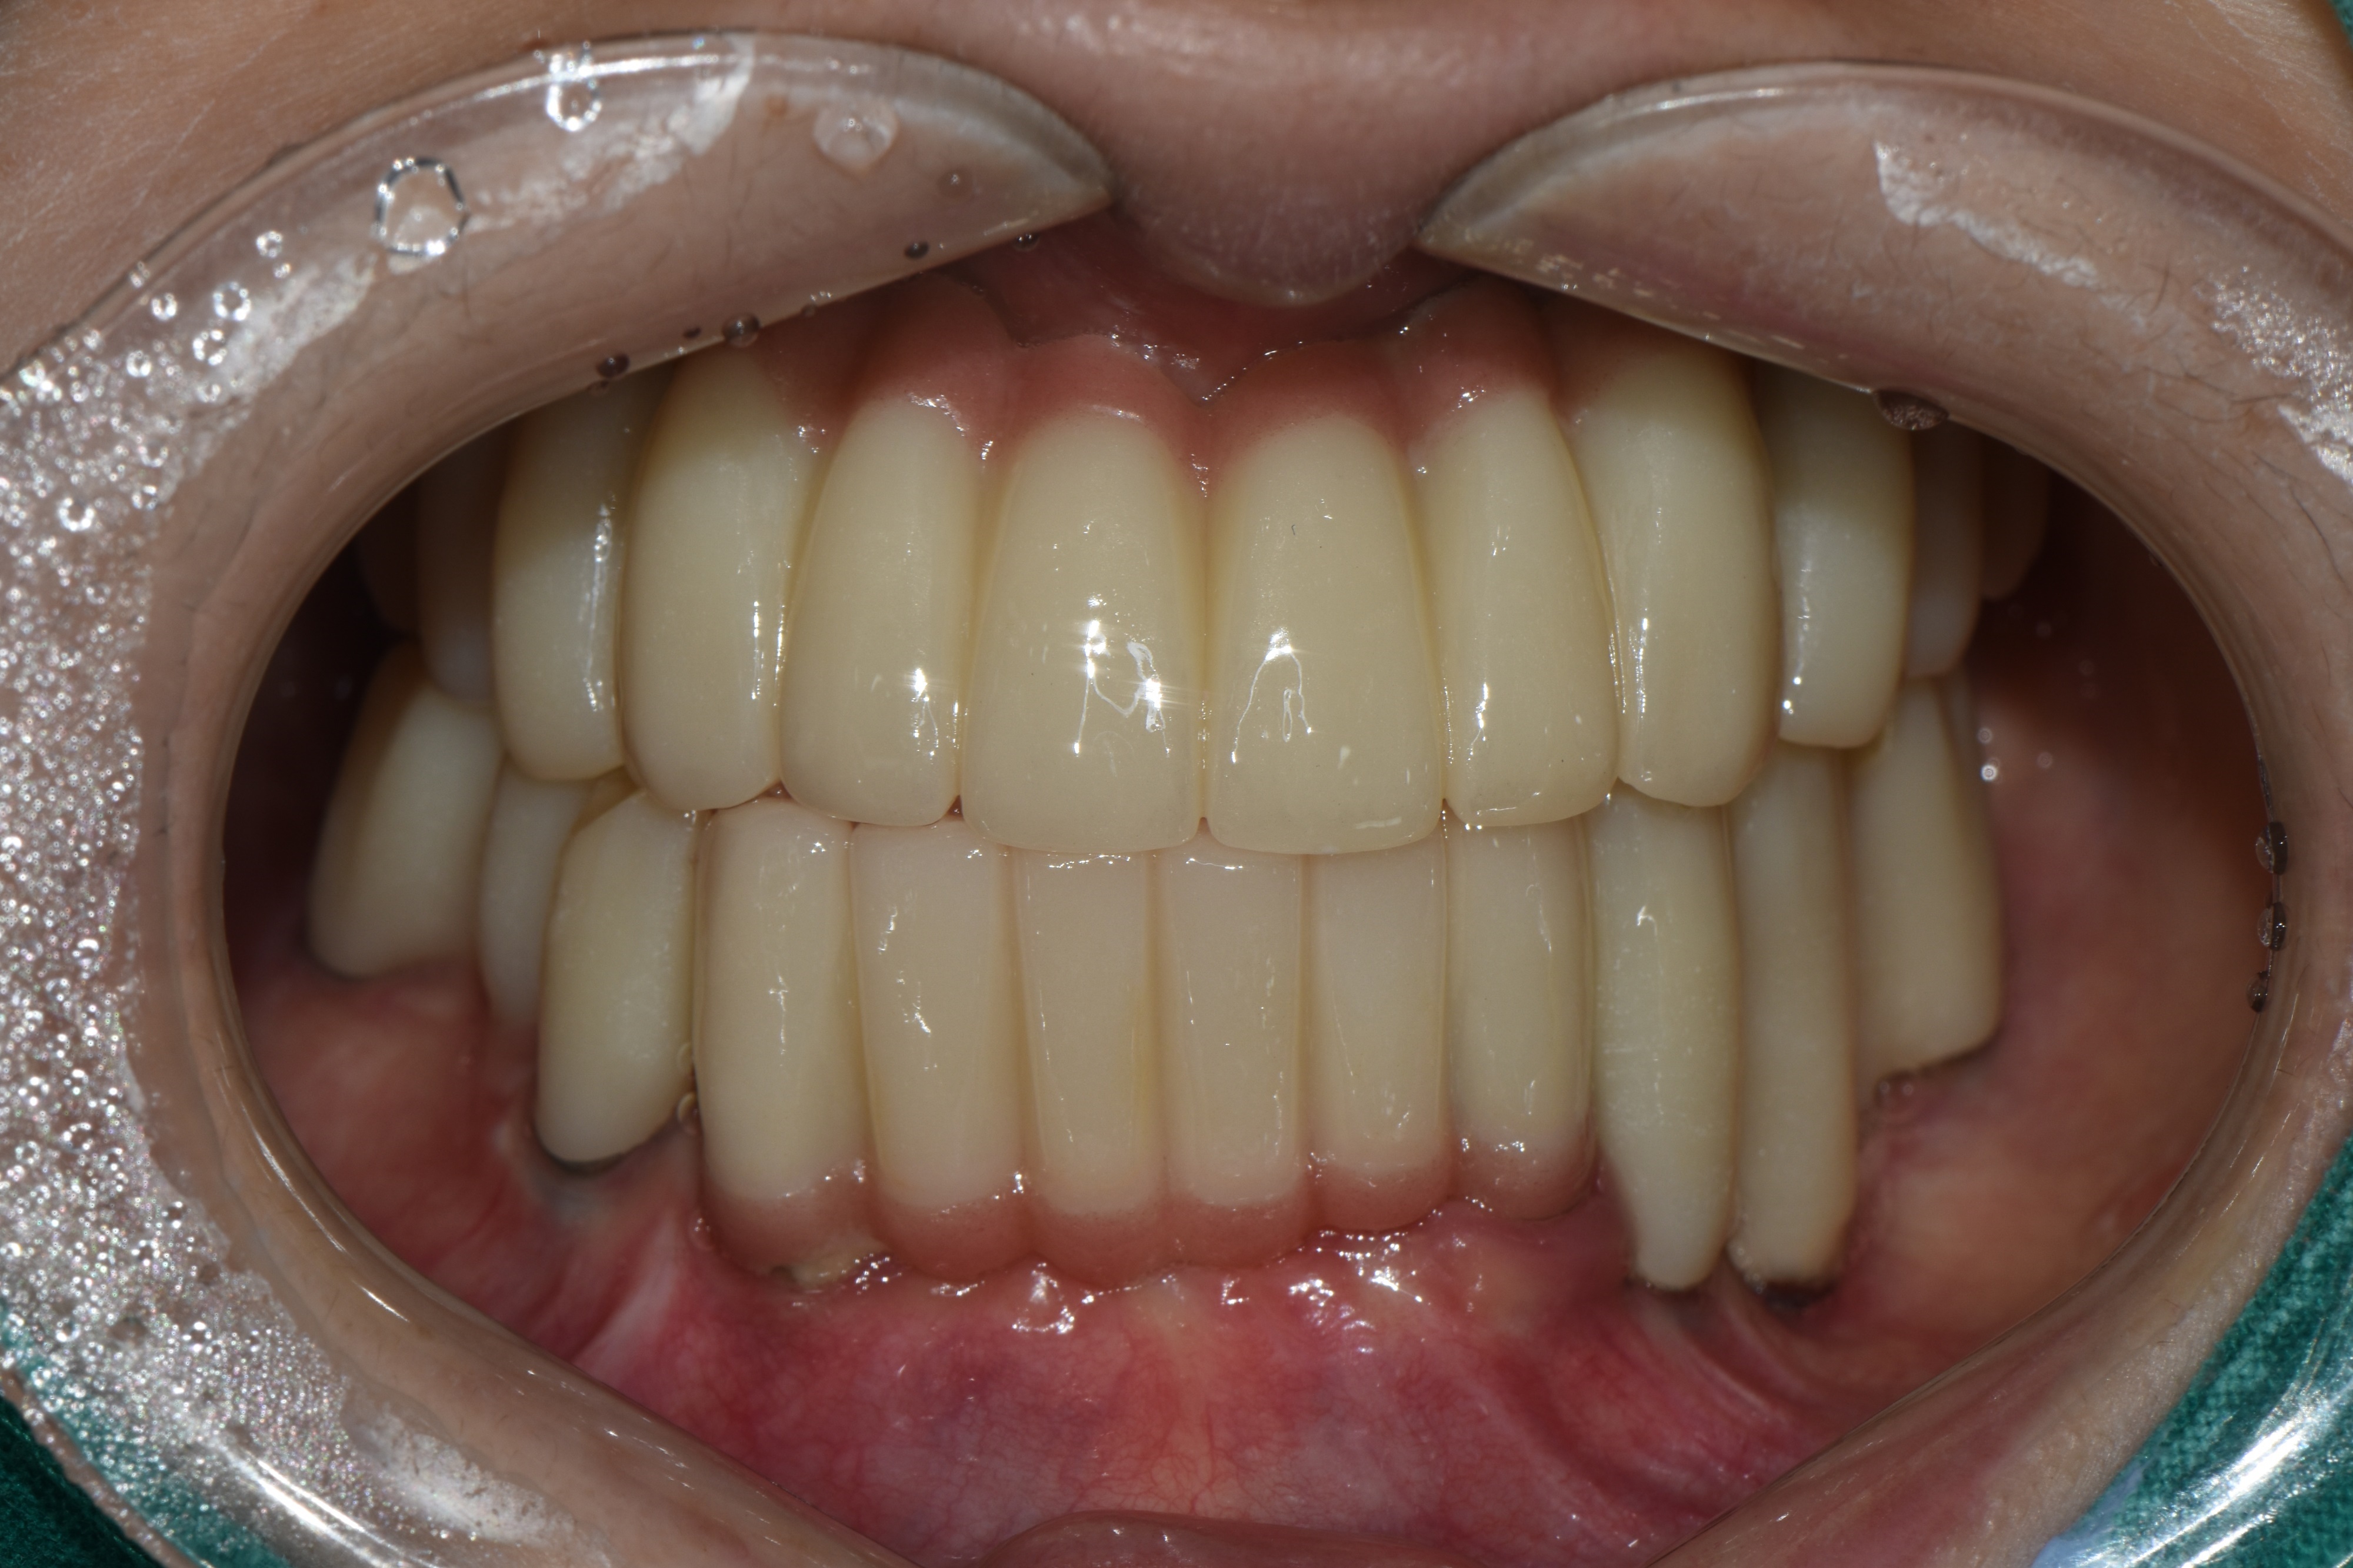

촬영일시: 2024.05.02

촬영일시: 2025.02.19 [ 치료기간: 2024년 05월 02일 ~2025년 02월 19일 ] ※ 365서울앞선치과의원의 모든 컬럼은 각 진료과 의료진이 직접 작성합니다. 365서울앞선치과의원 임상 케이스 게시물은 환자분께 의학적으로 정확하고 상세한 정보를 드리기 위해 각 진료과 의료진이 직접 작성하며, 모든 증례 사진은 본원 의료진이 직접 시술한 증례를 촬영한 것으로, 의료법 제23조, 제56조에 의거하며 환자분의 동의를 얻어 포스팅에 사용하였습니다. 또한 해당 케이스는 본 환자분의 치료 결과이며, 환자 상태에 따라 치료의 결과는 달라질 수 있습니다. |